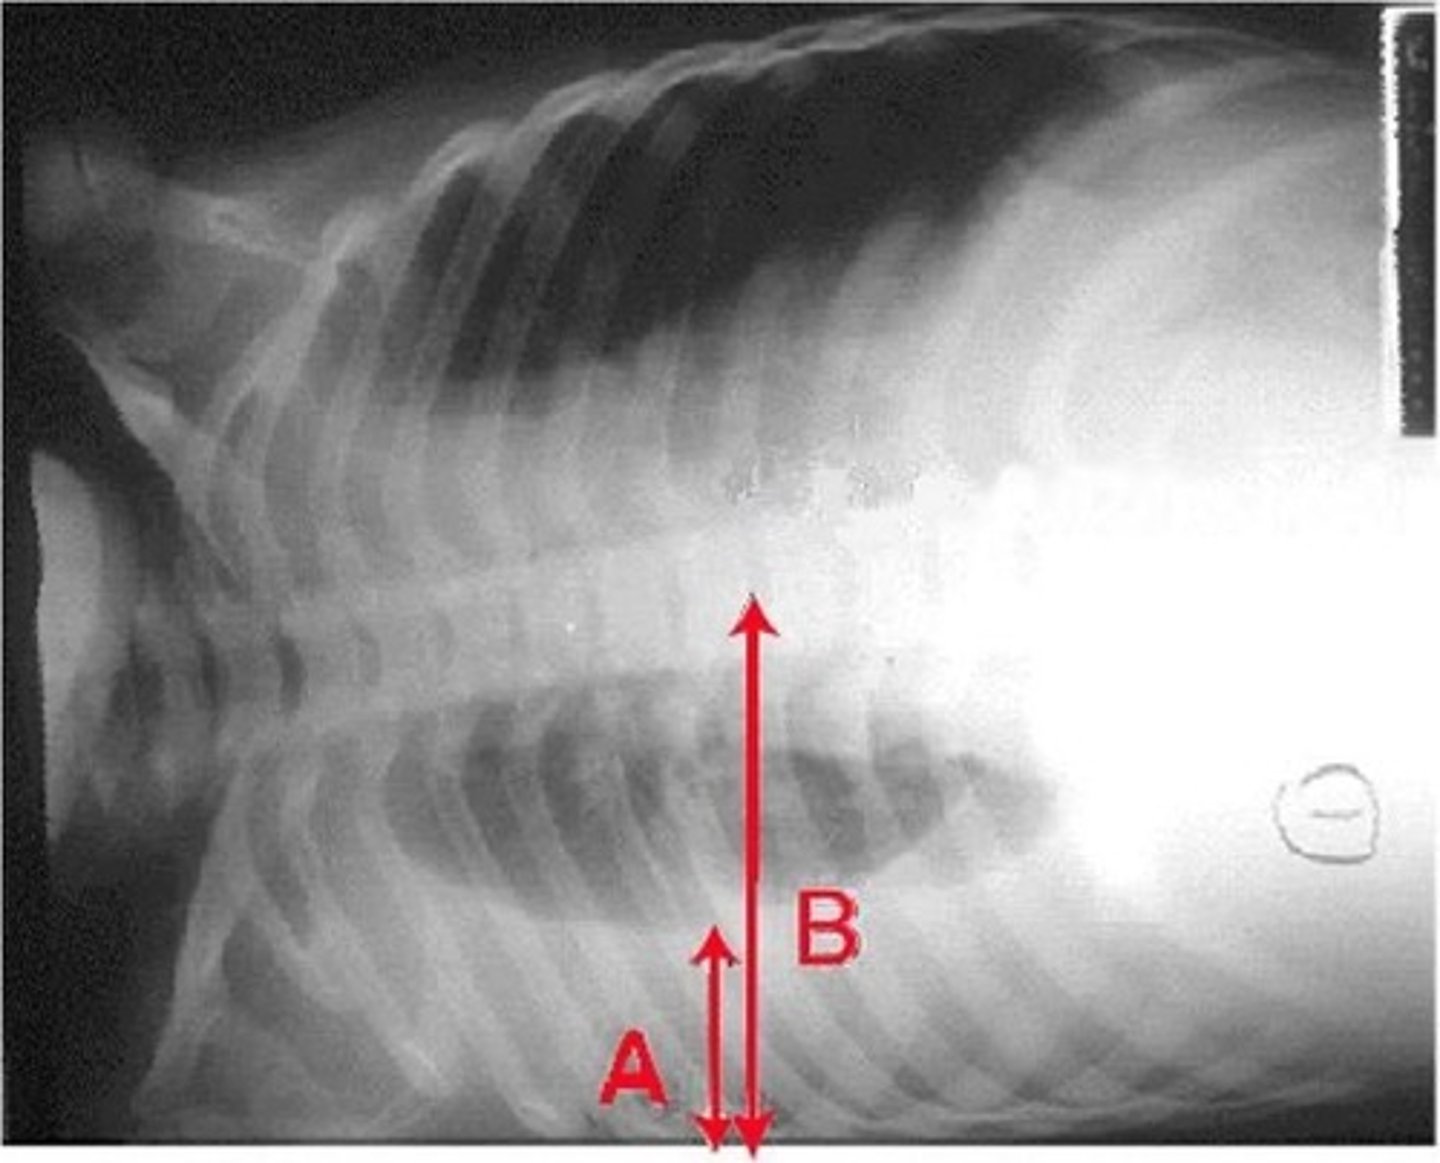

-pleural effusion (fluid will go to the bottom)

-pneumothorax (air will rise to top)

Lateral decubitus view is helpful in diagnosing what

lateral decubitus view